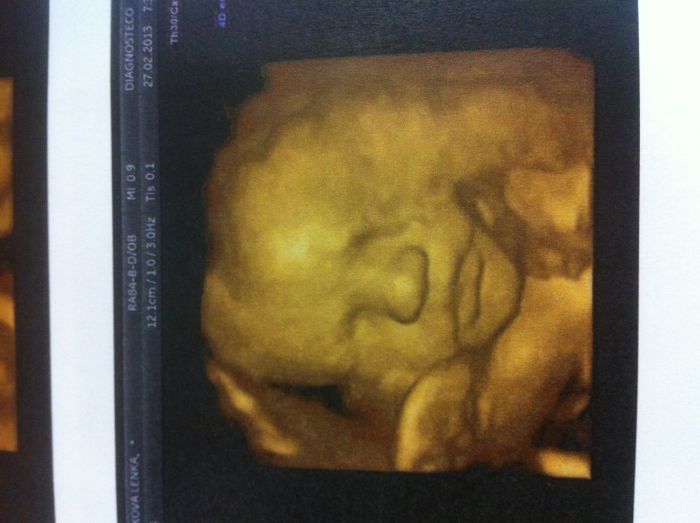

Tak posilam fotecky Manolita, na jedne ma vyplazlej jazyk, na druhe je videt jeho chlouba ( holky taky se Vam zda tak velka jako nam ;)???? ) a na jedne je vaznej.

ahoj Leni, také myslím, že rozhodně není pochyb o tom, že to bude Muž